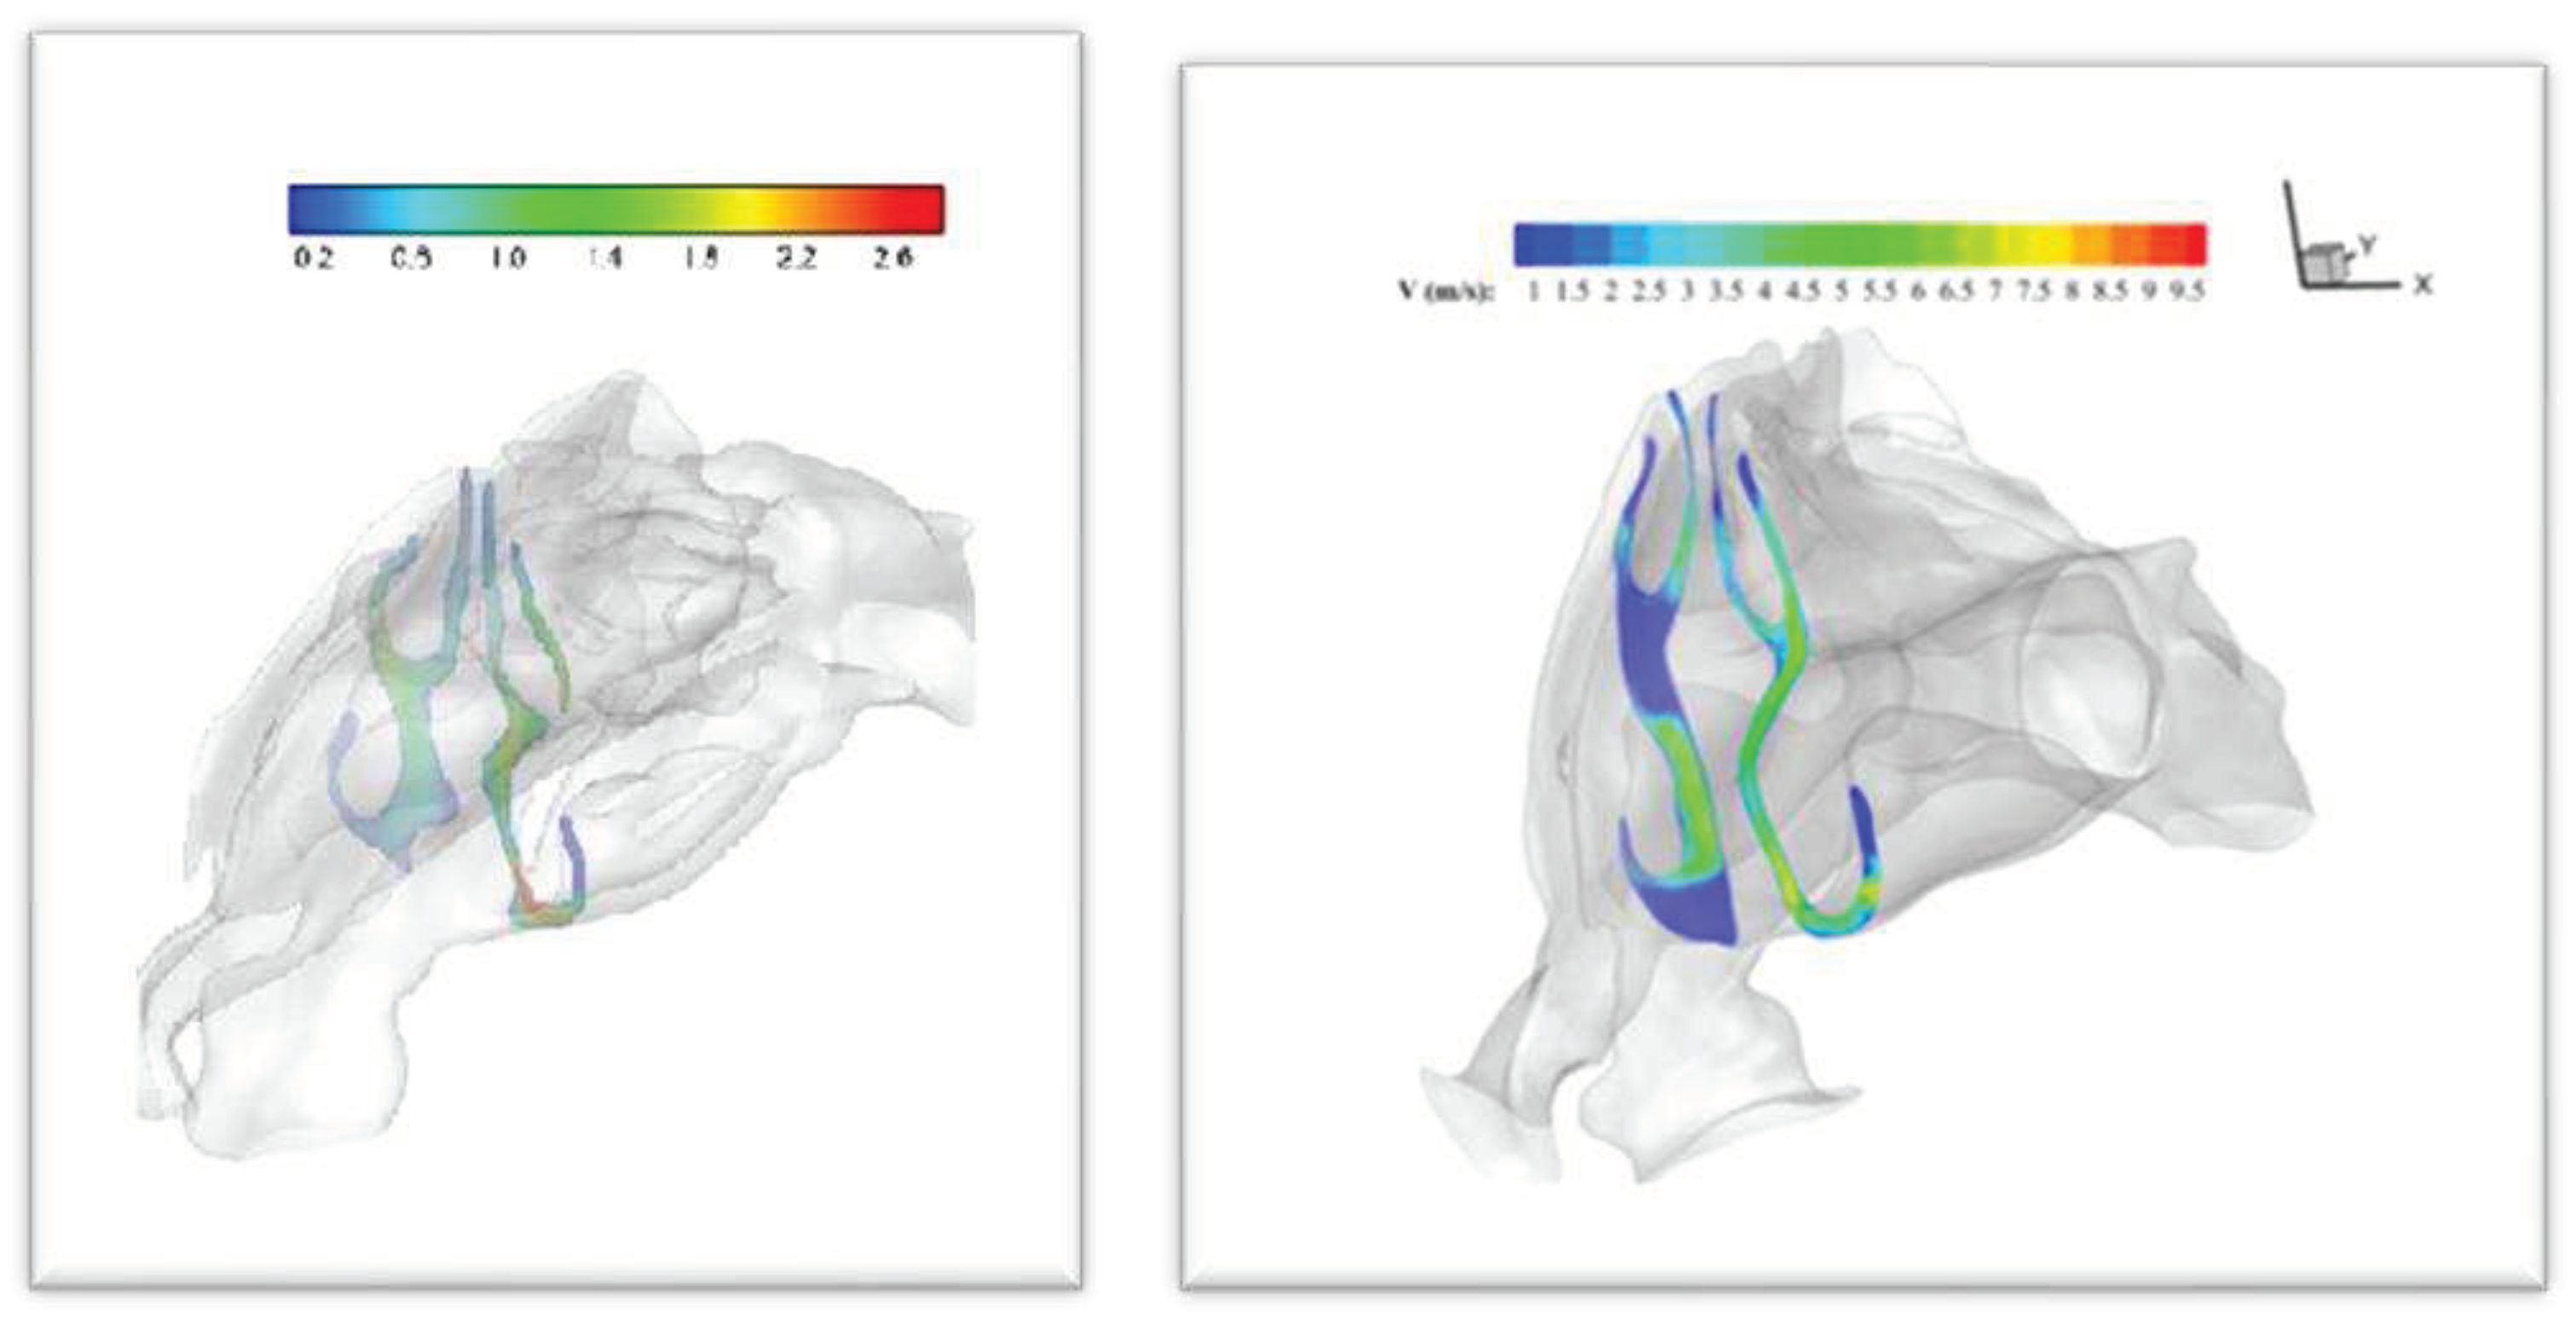

3.1. Velocity and Streamline Contours